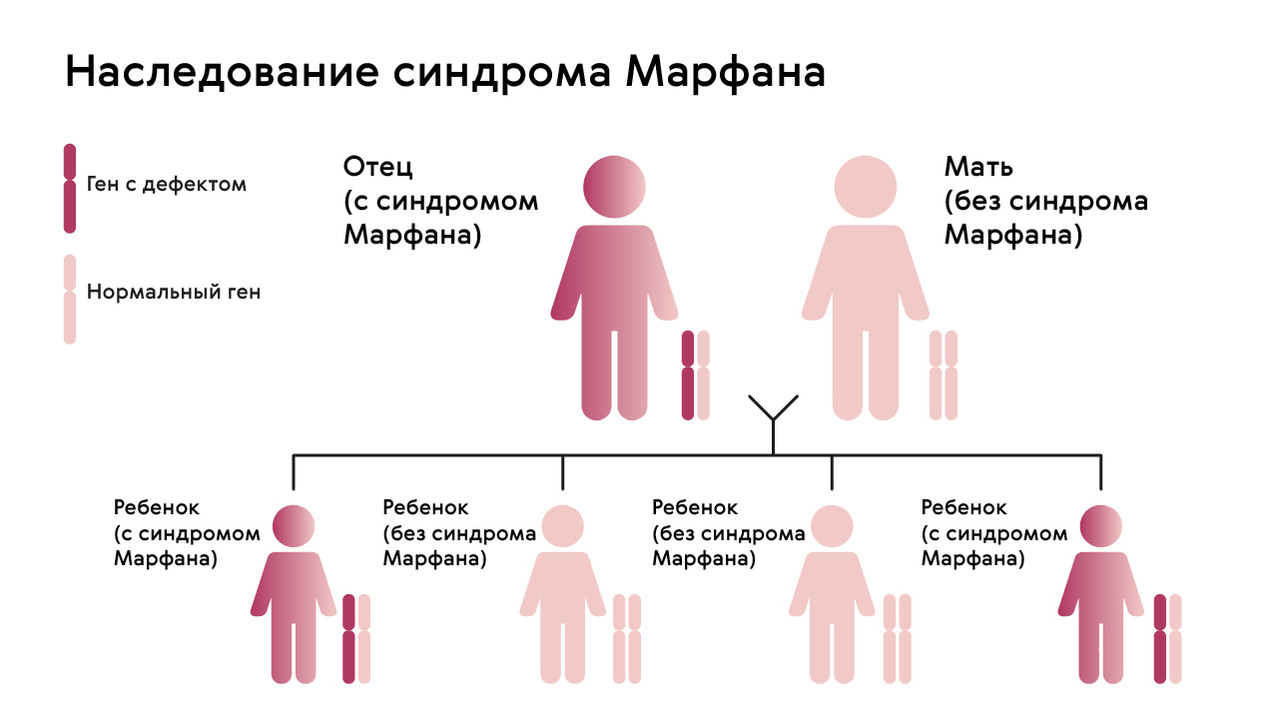

Boleznennyj dar nikkolo paganini redkij sindrom marfana priznaki sposoby lecheniya i nasledovanie u detej sindrom marfana kto bolel iz znamenitostej (Тип файлу jpg)

Boleznennyj Dar Nikkolo Paganini Redkij Sindrom Marfana Priznaki Sposoby Lecheniya I Nasledovanie U Detej Sindrom Marfana Kto Bolel Iz Znamenitostej

Chelovek i ego zdorove sindrom marfana sekrety andersena paganini i chukovskogo obsuzhdenie na liveinternet rossijskij servis onlajn dnevnikov (Тип файлу jpg)

Chelovek I Ego Zdorove Sindrom Marfana Sekrety Andersena Paganini I Chukovskogo Obsuzhdenie Na Liveinternet Rossijskij Servis Onlajn Dnevnikov